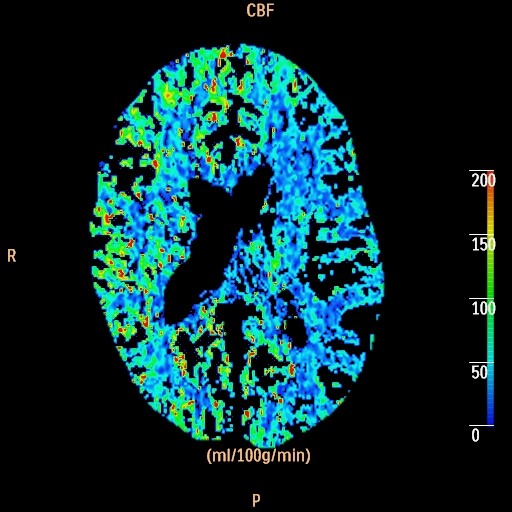

CT Perfusion scan for Radiology

How it works: CT Perfusion evaluates how well blood is flowing to the brain. A small bolus of iodine based intravenous contrast is injected rapidly through a vein, and then multiple low dose CT scans are taken through the same area of the brain to evaluate how the contrast bolus flows through a portion of the brain over time. The data is then processed with advanced perfusion software.

Equipment: Perfusion studies are usually performed on a Philips 64 or 256 channel CT scanner. OHSU is an ACR accredited CT facility.

Benefits: CT Perfusion is a fast, minimally invasive method of evaluating cerebral perfusion.  Reasons for the exam include evaluation of brain perfusion after stroke, temporary ischemic attack (TIA), and/or occlusion or narrowing of a major intracranial vessel.